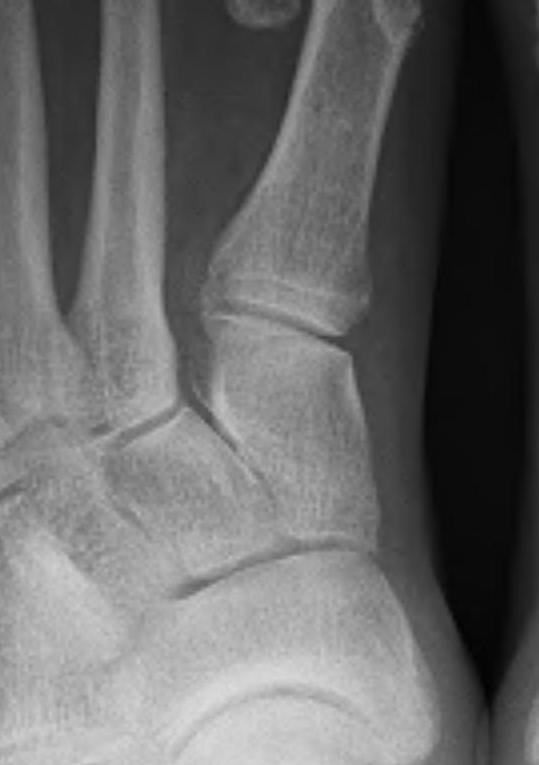

Other

| Joint congruence | Sesamoid subluxation | TMT joint obliquity |

|---|---|---|

|

Dots on articular surfaces - metatarsal head - base P1 |

Amount of lateral sesamoid uncovered |

Mann Classification

1. Congruent

2. Incongruent - mild / moderate / severe

3. Degenerative

Incongruent

| Mild | Moderate | Severe |

HVA < 30° IMA < 15° Lateral sesamoid < 50% uncovered |

HVA 30 - 40° IMA 15 - 20o Lateral sesamoid 50 - 75% uncovered |

HVA > 40° IMA > 20° Lateral sesamoid > 75% uncovered |